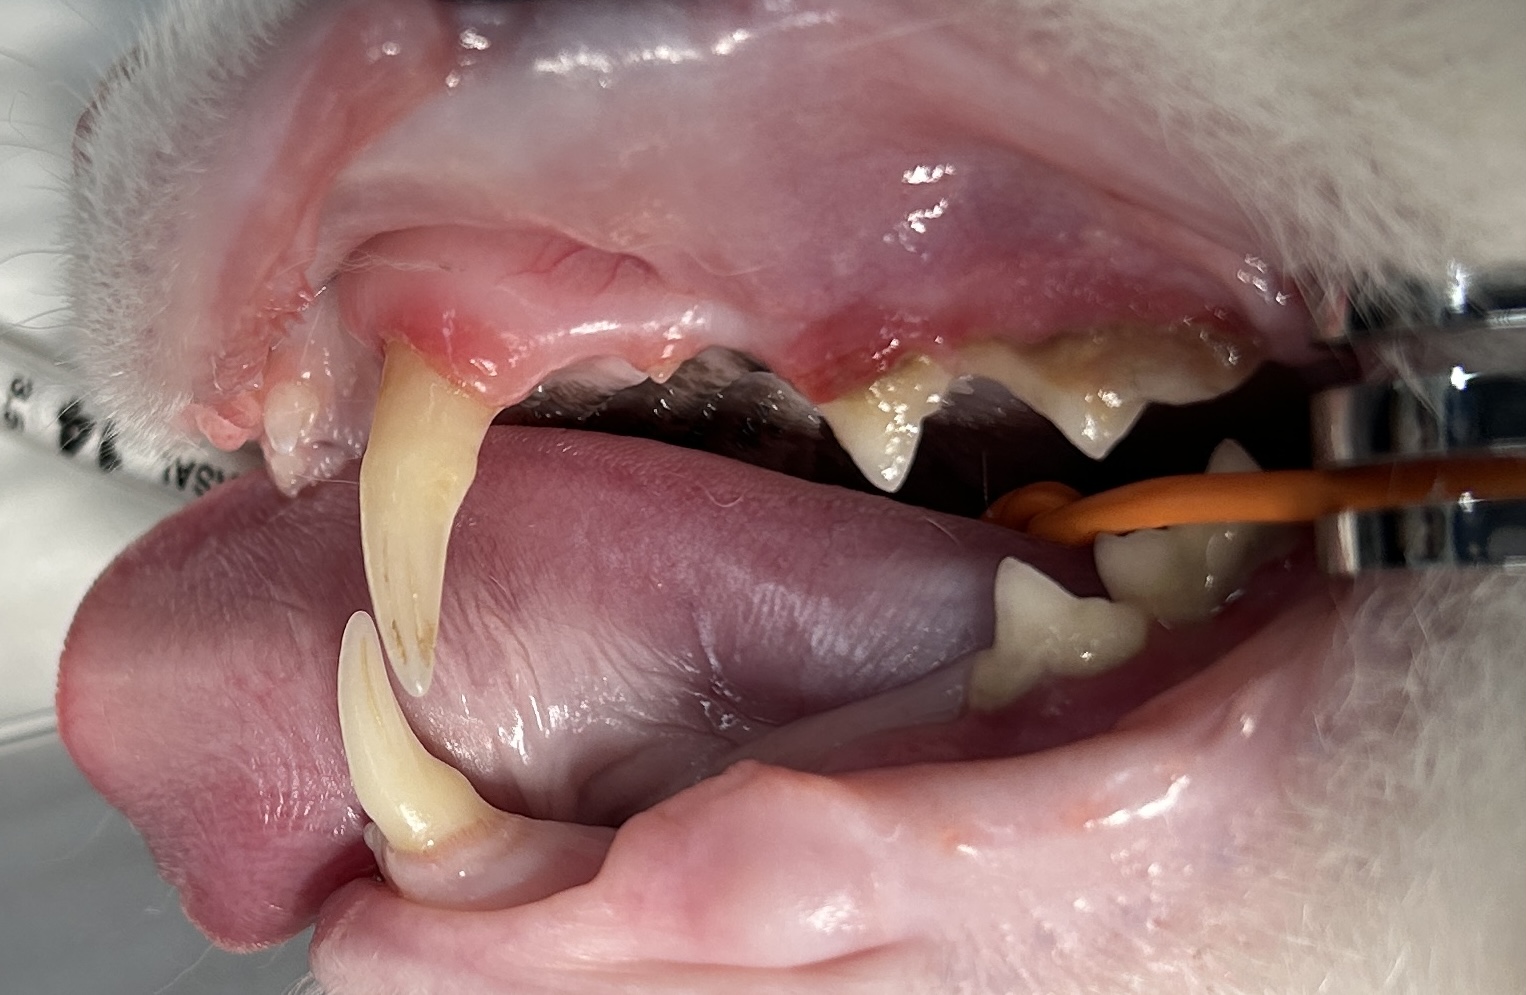

猫の吸収病巣

画面右側の上の歯と下の歯が一部吸収されている歯です。